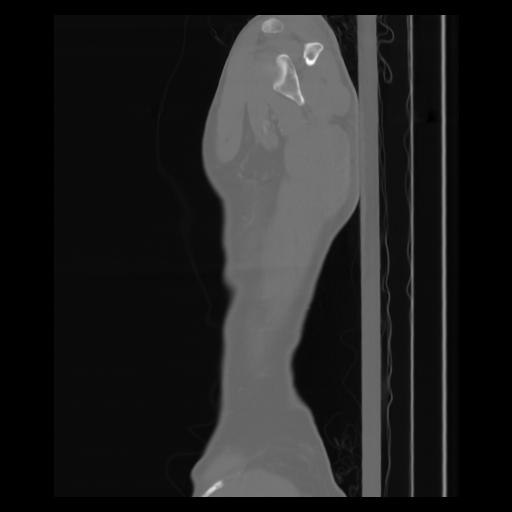

30 CUERPO,CE,Sagittal,3.000,CUERPO,Sagittal,